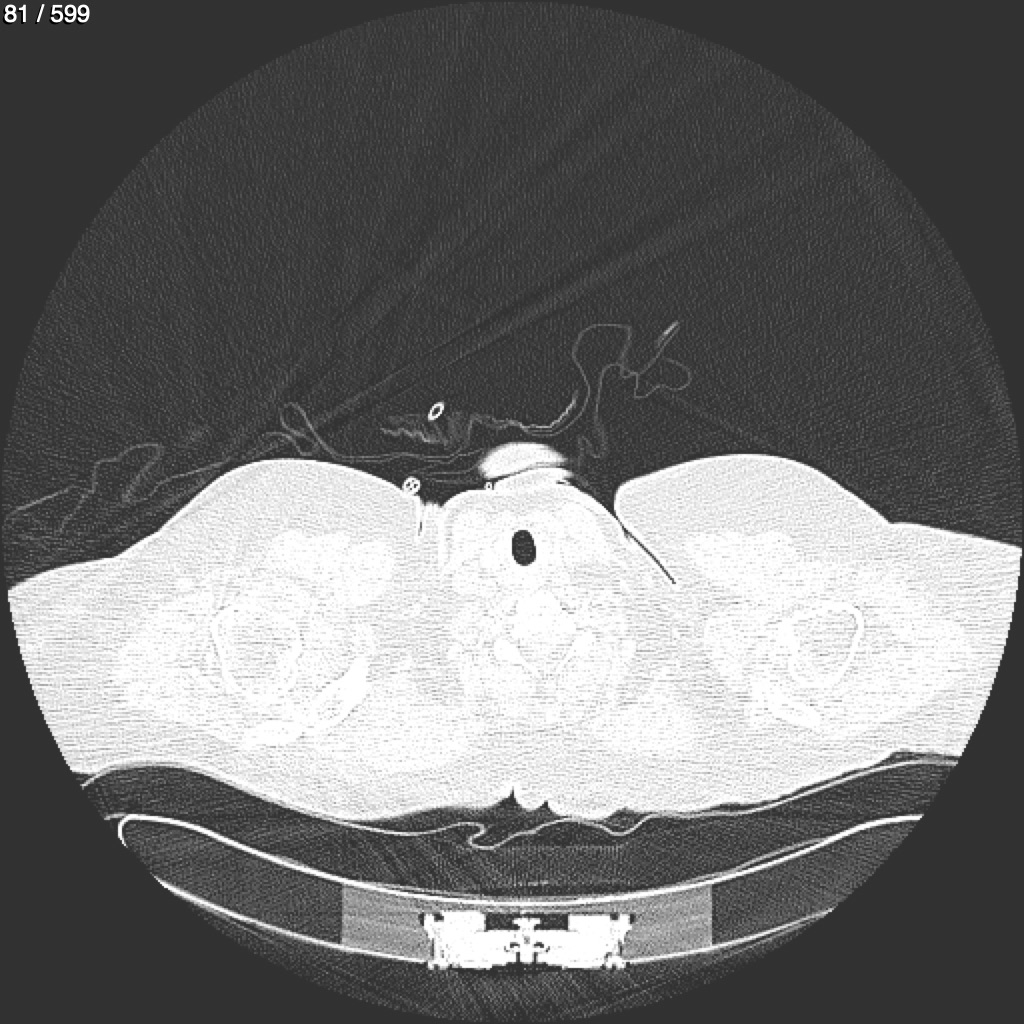

Home G​l​o​r​i​a​ ​G​l​a​d​y​s​ ​B​e​a​s​l​e​y​ ​-​ ​T​ó​r​a​x​ ​T​o​r​a​x​_​S​i​m​p​l​e​ ​(​A​d​u​l​t​o​)